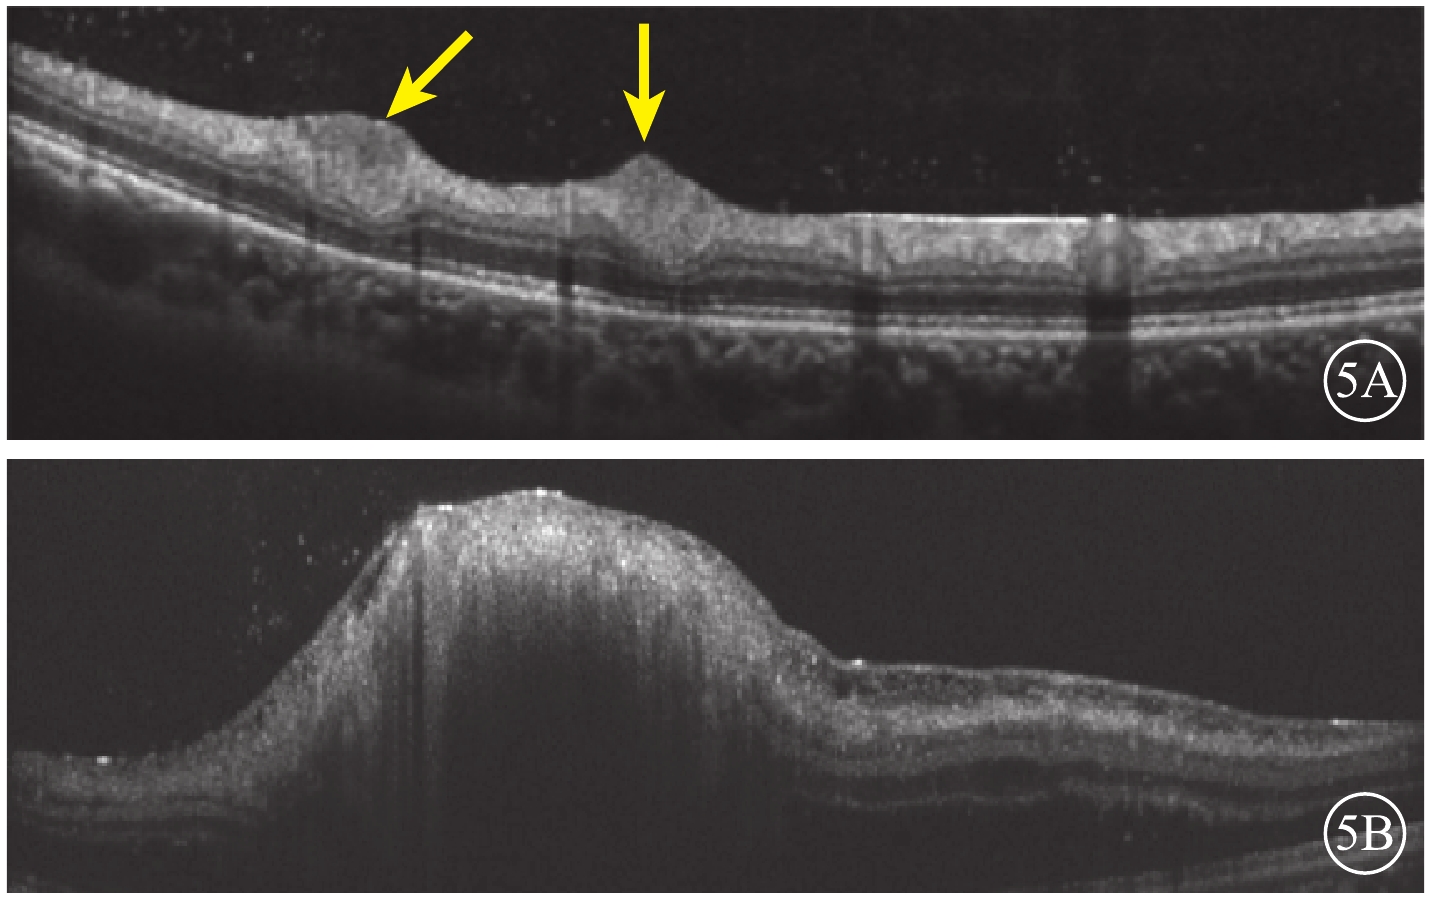

紅外眼底成像(IR)檢查,左眼視盤下方隆起病灶,結構紊亂,視盤上方可見兩處類橢圓形病灶(圖4A,4B)。光相干斷層掃描(OCT)血管成像(OCTA)檢查,左眼視盤下方病灶周邊部分可見血流,其余小病灶未見明顯異常(圖4,4D)。結合病史及輔助檢查,診斷為結節性硬化并發視網膜星形細胞錯構瘤。OCT檢查,左眼視盤下方視網膜光帶呈圓頂狀隆起,光帶增寬且反射增強,病灶內呈蟲蝕狀,各層結構不清,周圍視網膜層間水腫伴神經上皮脫離,其余各病灶對應區域OCT斷面上視網膜內層光帶增厚隆起,反射增強(圖5)。

圖5

患者左眼OCT像。5A.與圖4A對應病灶處視網膜內層光帶增厚隆起,反射增強(黃箭);5B.與圖4B對應病灶處可見隆起,結構紊亂

圖5

患者左眼OCT像。5A.與圖4A對應病灶處視網膜內層光帶增厚隆起,反射增強(黃箭);5B.與圖4B對應病灶處可見隆起,結構紊亂

紅外眼底成像(IR)檢查,左眼視盤下方隆起病灶,結構紊亂,視盤上方可見兩處類橢圓形病灶(圖4A,4B)。光相干斷層掃描(OCT)血管成像(OCTA)檢查,左眼視盤下方病灶周邊部分可見血流,其余小病灶未見明顯異常(圖4,4D)。結合病史及輔助檢查,診斷為結節性硬化并發視網膜星形細胞錯構瘤。OCT檢查,左眼視盤下方視網膜光帶呈圓頂狀隆起,光帶增寬且反射增強,病灶內呈蟲蝕狀,各層結構不清,周圍視網膜層間水腫伴神經上皮脫離,其余各病灶對應區域OCT斷面上視網膜內層光帶增厚隆起,反射增強(圖5)。

圖5

患者左眼OCT像。5A.與圖4A對應病灶處視網膜內層光帶增厚隆起,反射增強(黃箭);5B.與圖4B對應病灶處可見隆起,結構紊亂

圖5

患者左眼OCT像。5A.與圖4A對應病灶處視網膜內層光帶增厚隆起,反射增強(黃箭);5B.與圖4B對應病灶處可見隆起,結構紊亂

討論 結節性硬化病是一種少見的以皮膚、腦、腎、眼等多系統錯構瘤為特征的綜合征[1]。本例患者存在皮膚纖維斑塊,面部纖維血管瘤、指甲纖維瘤、腎臟錯構瘤、視網膜錯構瘤等多項主要特征。說明其結節性硬化病診斷成立[1]。視網膜星狀細胞錯構瘤是結節性硬化病的常見眼部病變,多表現為多灶性和雙側性[2]。根據形態學分型,視網膜星狀細胞錯構瘤可分為小的半透明平滑病灶(Ⅰ型)、大的鈣化結節病灶(Ⅱ型)和兩種病灶混合存在(Ⅲ型)3種類型[3]。本例患者Ⅰ型、Ⅲ型病灶并存。左眼視盤下方的大病灶為Ⅲ型病灶,病灶周圍并發滲出性視網膜脫離及視網膜層間水腫,這可能與病灶處存在牽拉、血視網膜屏障遭到破壞有關;其余各病灶均為Ⅰ型病灶。

我們對本例患者行多模式影像檢查。OCT可清晰顯示病灶細節及所在的視網膜層次。OCTA檢查提示瘤體內含血管成分,故FFA顯示病灶晚期熒光素滲漏;由于各病灶血管含量及通透性不一致,故熒光素滲漏情況存在差異。左眼視盤下方病灶較厚,對視網膜色素上皮形成遮擋,因此在FAF上呈現弱AF,其余各病灶均未見明顯異常AF改變。超廣角眼底彩色照相成像范圍廣,眼底各個病灶均可觀察到。IR可較清晰觀察到病灶,并與OCT實時對應,輔助OCT定位掃描。我們分析超廣角眼底彩色照相、IR及OCT之所以能夠較明顯地觀察到病灶的原因是,均為單一波長激光,反射后聚焦在同一點上,組織對其吸收較少,故可得到更清晰的圖像[3]。三者結合可以更全面細致地觀察視網膜星狀細胞錯構瘤各病灶,既利于臨床高效診斷及鑒別診斷,又便于對病灶進行長期觀察。